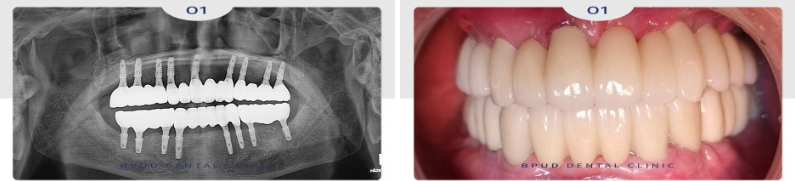

25.01.16

부평역치과 전체임플란트 치료 후

환자분께서는 자신감을 회복하셨고

식사도 잘하신다며 만족해하셨습니다!